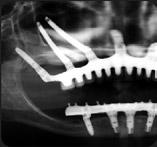

Can Ruti tracta la hipertensió col·locant un dispositiu d'ultrasons per primera vegada a Espanya

L'Hospital Germans

Trias ha donat un pas més en la seva capacitat i lideratge arreu de l'Estat pel que fa a tractar una de les malalties amb més prevalença del món: la hipertensió arterial, que afecta a la meitat o més de la població major de 50 anys. I és que Can Ruti ha realitzat amb èxit el primer procediment per abordar aquesta patologia amb una tècnica pionera a Espanya: col·locant en el pacient, un home de 74 anys, un dispositiu que, mitjançant l'emissió d'ultrasons, modula l'activitat del sistema nerviós simpàtic, un dels encarregats de la regulació de la pres-

sió arterial. En concret, aquest dispositiu forma part de la tècnica de la denervació renal, en què la Unitat de Cardiologia Intervencionista de l'hospital és referent a nivell estatal i internacional. Segons els experts, aquest tècnica

"és mínimament invasiva pels pacients, té un risc de complicació mínim i aconsegueix disminuir l'activitat nerviosa simpàtica i ajudar a controlar la pressió arterial, sobretot en pacients en què la medicació no fa efecte".